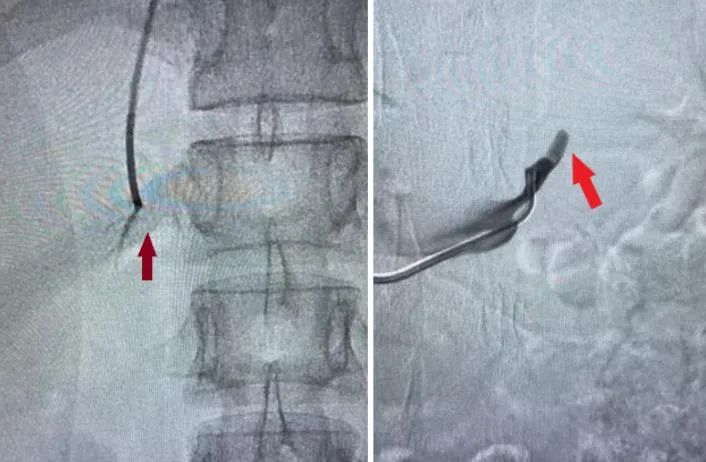

▲肾上腺静脉采血术

▲导管到达右肾上腺静脉(左图);导管到达左肾上腺静脉(右图)。